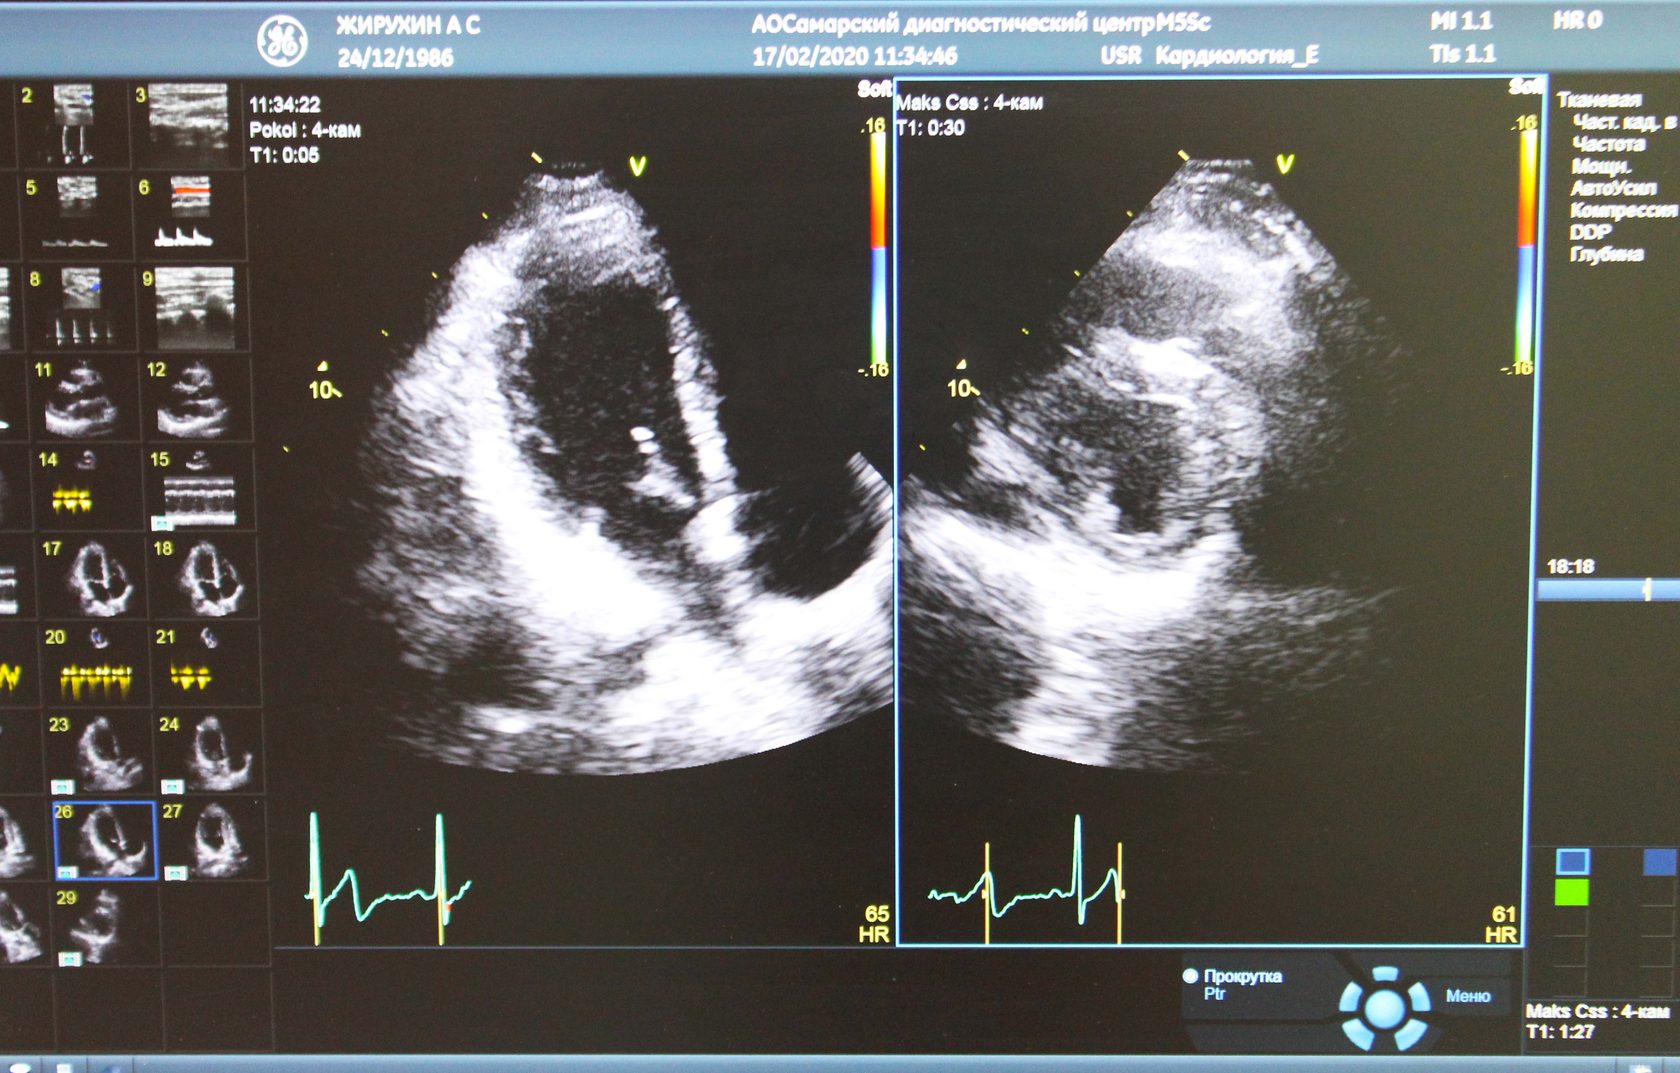

За одним стрессом следует другой. Одно из самых необычных, новых и информативных исследований - Стресс ЭХОКГ. Говоря по-простому, медики исследуют, как поведет себя сердце человека при повышенных нагрузках. Нагрузку создают с помощью специального велотренажера, на котором можно регулировать мощность.

Для начала врач исследует сердце пациента в спокойном состоянии. Делает УЗИ, исследует сосуды.

Аппарат сохраняет данные для того, чтобы сравнить их потом, когда сердце будет под нагрузкой и в состоянии отдыха после нагрузки.

Затем дается нагрузка на сердце: Алексей выжимает максимальную мощность из педалей.

Прямо во время тренировки врач повторно делает УЗИ сердца и смотрит на его состояние при физической активности.

Во время исследования Алексей заметно устает, но рад тому, что выдержал максимальный темп. Если бы у него были начальные признаки ишемической болезни сердца, то Стресс-ЭХОКГ их бы выявило.